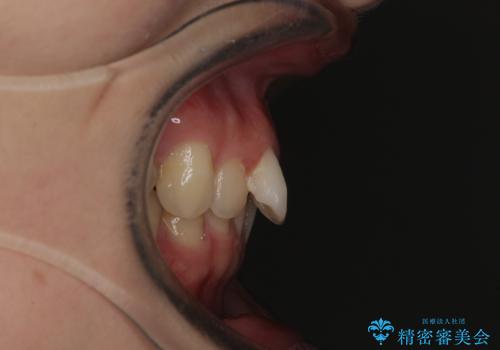

ぱっと見はインビザラインによる矯正治療も可能と思われましたが、歯根が最も長い犬歯がクロスバイトになっており、インビザラインでは対応困難と判断され、ワイヤー装置にて矯正治療を行うこととしました。

クロスバイトになっている犬歯は、歯の移動に伴い装置を張り替えていくことで対応することとしました。

クロスバイト改善中には歯髄壊死を起こすリスクがあるため、神経に問題がないか確認しながら治療を進めて行く必要があります。

思っていたよりも早くクロスバイトは改善され、歯髄壊死に至ることなく、無事に治療を終えることができました。